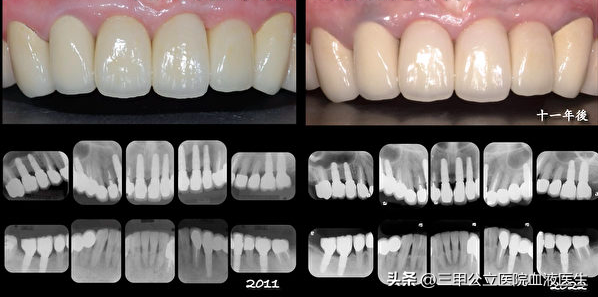

第一:種植牙為什么會失???種植牙的問世,已經(jīng)十幾年了, 在國外已經(jīng)有多的成功案例, 然而這種技術(shù),推廣到我國,雖然給很多愛美的個(gè)體,帶來了足夠好的美感, 但是由于個(gè)體已經(jīng),技術(shù),甚至材料上的差異,直接造成很多人種植牙失敗,

成功的種植牙有舒適美觀、穩(wěn)固牢靠、持久三大優(yōu)勢,能修復(fù)恒牙缺失,重建咀嚼功能,提高人類生存質(zhì)量,因此種植牙被譽(yù)為“人類的第三副牙齒”